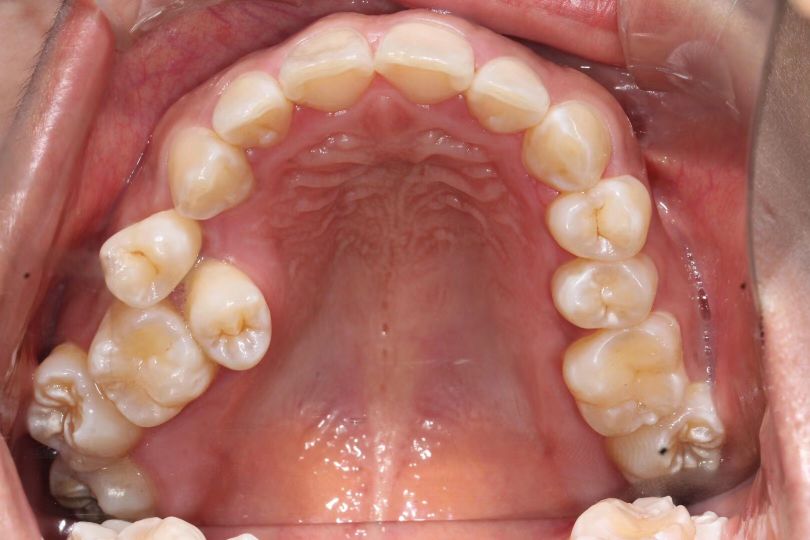

- 首先要找靠谱的医生去面诊,详细了解一下自己 的情况,面诊检查【拍片、照相、取牙模】 后面有详细介绍

- 其次检查口内是否有虫牙(有的话做矫正之前必须补)是否有 结石(洁牙洁牙洁牙),是否有种植牙等其他牙齿问题

PS: 前期准备工作包括(全景片 ,头颅侧位片 ,CT ,6张口内 照片,6张面相照 , 模型,补牙,洁牙…)